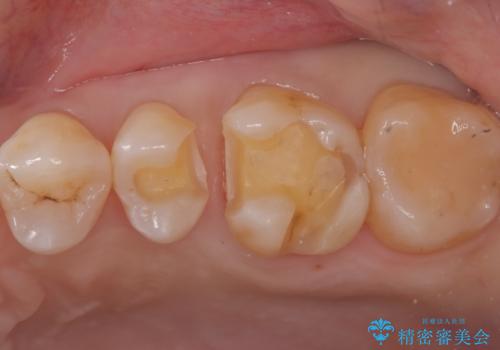

- 左上5番と6番の奥歯に入っている金属の詰め物(メタルインレー)の見た目を改善したいという主訴でご来院されました。お口の中の金属をなくしたいという患者様のご希望を踏まえ、天然歯に近い色と質感を持つセラミックインレーに交換する治療計画を立案。これにより、見た目の改善だけでなく、金属アレルギーのリスクを排除したメタルフリーの環境を実現することを目指しました。

治療では、まず古い金属のインレーを慎重に取り外しました。金属の下に隠れていた虫歯の再発がないかを確認し、歯を丁寧に形成。その後、精密な型取りから患者様の歯の色に合わせたオーダーメイドのセラミックインレーを作製しました。セラミックは、自然な光の透過性を持つため、周囲の歯と区別がつかないほどの美しい仕上がりとなります。適合性の高いセラミックインレーを装着することで、再発のリスクを抑えつつ、長年のコンプレックスだった銀歯がなくなり、笑顔でも気にならない自然な奥歯を取り戻していただけました。